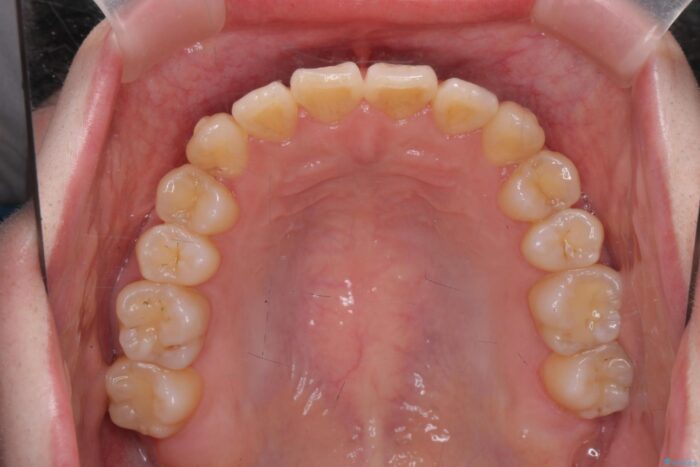

前歯のねじれが気になる、歯並びを改善したいとご来院された患者様です。

歯のねじれをきれいに取るのは、インビザライン(マウスピース矯正)だけでは難しい動きです。そのため、事前に4か月間の部分ワイヤー矯正を行い、治療期間を短くし、より美しい仕上がりを目指す計画です。